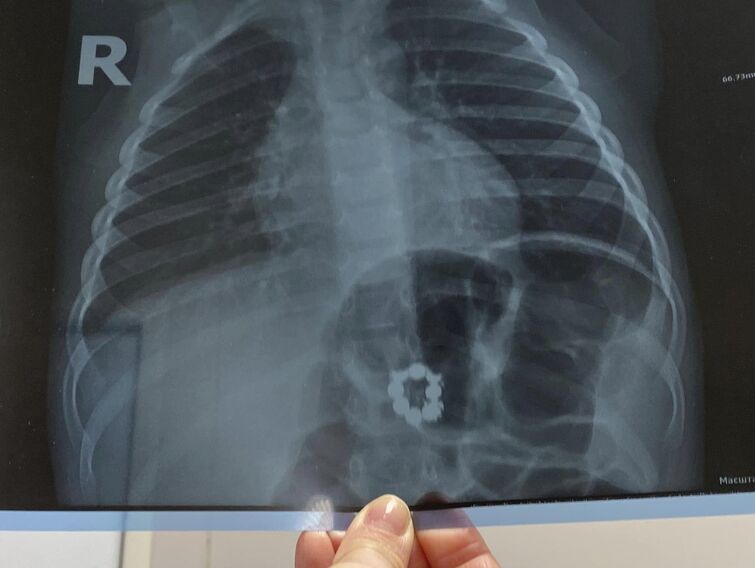

"Під час обстеження малюка у педіатра, лікар призначив рентген-знімок, на якому побачили неприємну знахідку – 8 магнітів, замкнутих в коло", – розповідають медики.

Де хлопчик знайшов магніти – невідомо, адже, за словами батьків, вдома таких іграшок немає. Родину терміново відправили в Охматдит. Там, під час дообстеження лікарі виявили чотири сторонніх предмети у шлунку, а решту – поза ним.